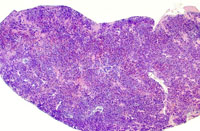

A higher magnification of hepatic erythroleukemia.

Examples of erythroleukemia in a Tg.AC mouse.